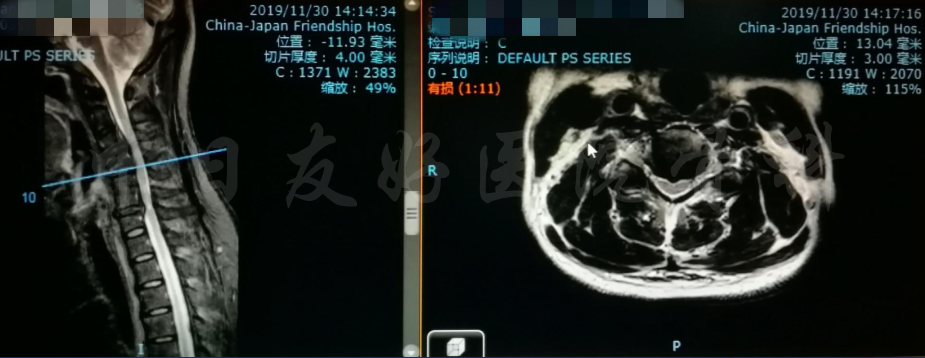

MRI

MRI颈4-5(左)、颈5-6(中)颈6-7(右)

矢状位MRI

轴位MRI:腰3-4(左)、腰4-5(中)、腰5骶1(右)

2019年11月30日 颈椎MRI提示:颈3/4颈4/5颈6/7椎间盘突出,椎管狭窄;颈5-6水平脊髓异常信号,变性可能。

颈椎MRI

颈椎MRI

颈椎各节段MRI(上下滑动)